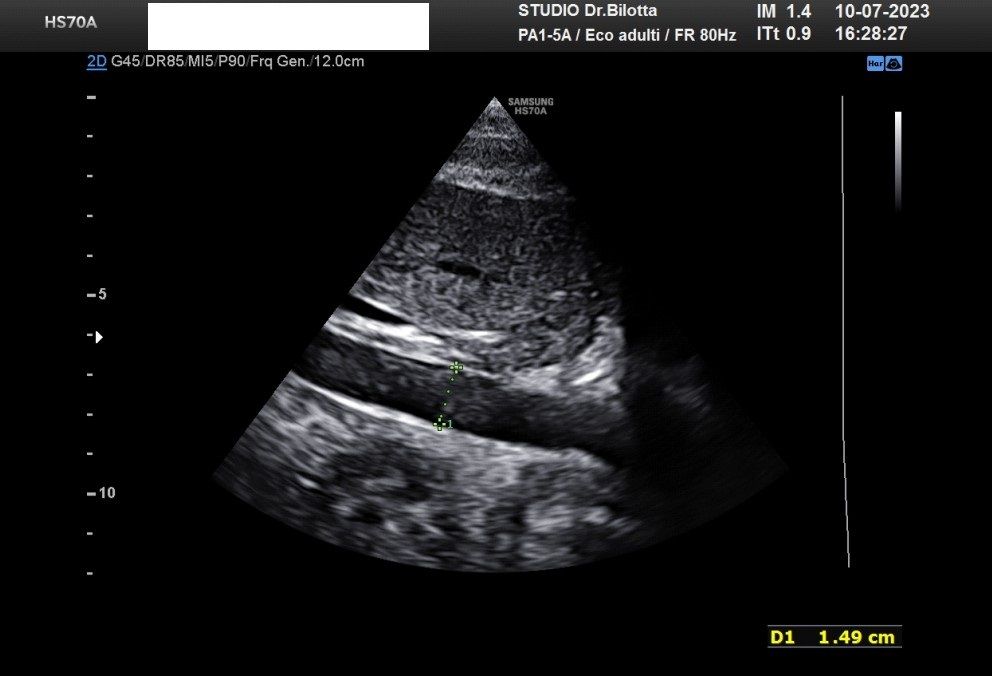

Diploma di maturità classica. Laurea in Medicina e Chirurgia con Lode a 26 anni. Specialista in Oncologia Generale Diagnostica e Preventiva con Lode a 31 anni. Specialista in Malattie Cardiovascolari a 36 anni. Medico generalista dal 1990 poi ospedaliero per trent'anni dal 1993 al 2022 nel corso dei quali ho refertato oltre 100 mila tracciati elettrocardiografici, effettuato oltre 30 mila consulenze specialistiche, praticato circa 10 mila esami ecocardiografici, condotto oltre 2 mila test ergometrici sia su cicloergometro che su treadmill, visionato circa 1500 esami Holter Ecg e ABP ( Ambulatory Blood Pressure ) occupandomi prevalentemente di prevenzione cardiovascolare, ipertensione arteriosa, cardiopatia ischemica, valvulopatie. Dal 2023 ho deciso di trasferire le mie competenze nella libera professione presso il mio studio privato che è stato allestito in linea alle moderne esigenze tecnologiche. Metodiche diagnostiche attualmente praticate: Elettrocardiografia a riposo, Ecocardiografia mono-bidimensionale, PW, CW, Colordoppler tridimensionale, GLS Strain Speckle tracking, Monitoraggio Holter Pressorio delle 24 ore, Monitoraggio Holter ECG 12 canali dinamico delle 24 ore.

Foto e video